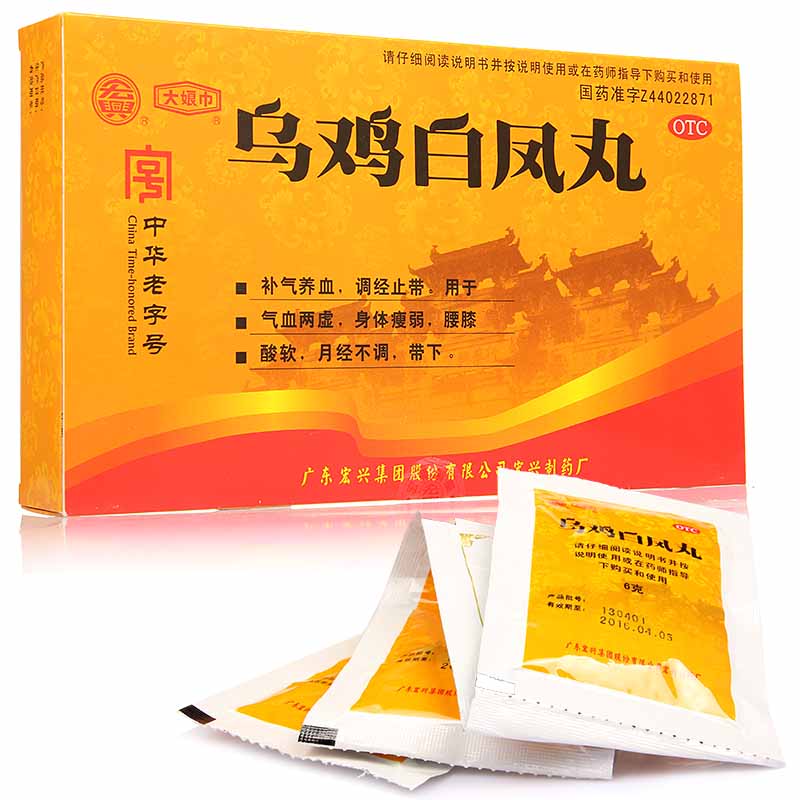

妊娠早期服用維A酸類、抗癲癇藥等致畸藥物可能導致畸形。備孕及孕期女性應嚴格遵醫囑用藥,禁用已知致畸藥物。